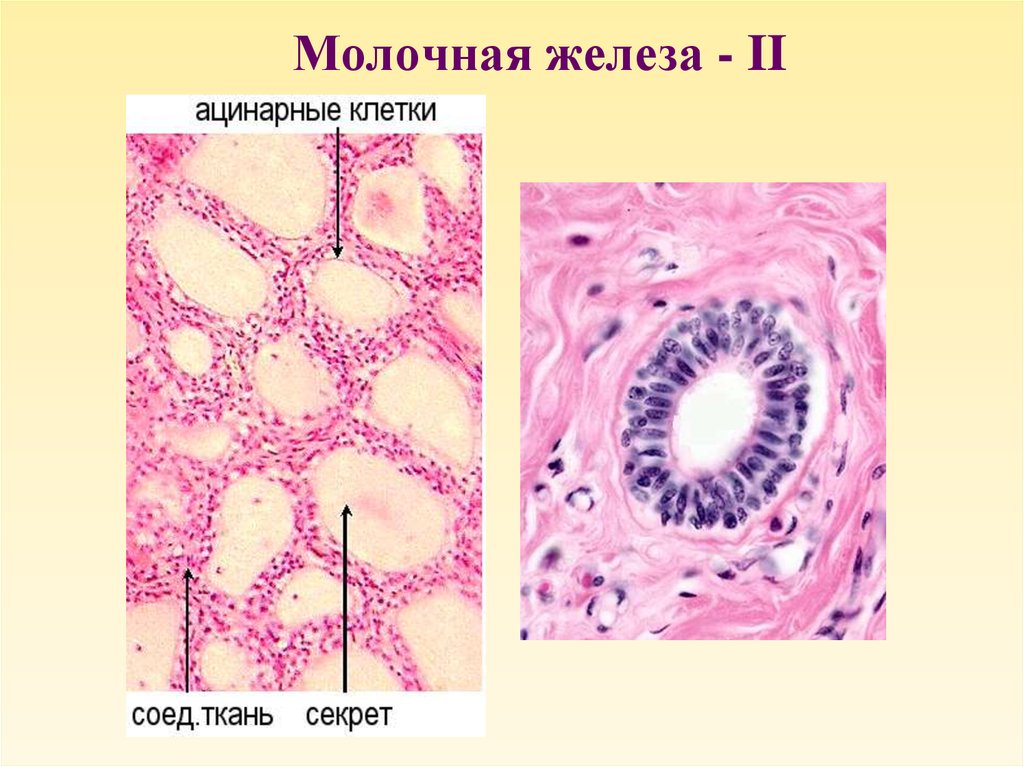

Исследование: микропрепарат молочной железы в медицине

Раздел: Снимки-откровения